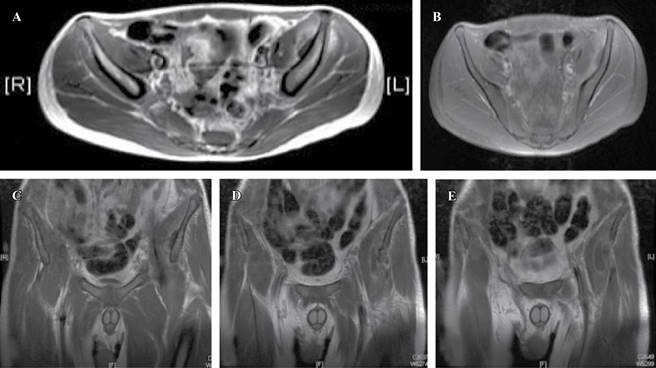

Se le solicitó una resonancia magnética contrastada de cadera donde se observa una colección adjunta a la Tabla interna del hueso ilíaco izquierdo, entre el espesor del músculo ilíaco izquierdo con extensión al músculo piriforme obturador y psoas mayor izquierdo. La lesión se caracterizaba por la presencia de septación y formación de un flemón junto con líquido inflamatorio y edema en el músculo ilíaco izquierdo (Figura 2).

Figura 2: Resonancia magnética nuclear contrastada en la que puede observarse a nivel del músculo ilíaco izquierdo la presencia de una colección en contacto con la Tabla interna del hueso ilíaco dentro del espesor y en la superficie del músculo ilíaco izquierdo (A y B). Nótese cómo el absceso se desplaza hacia el vientre del músculo psoas mayor en sentido inferior desde la Tabla interna del hueso ilíaco izquierdo (C-E).